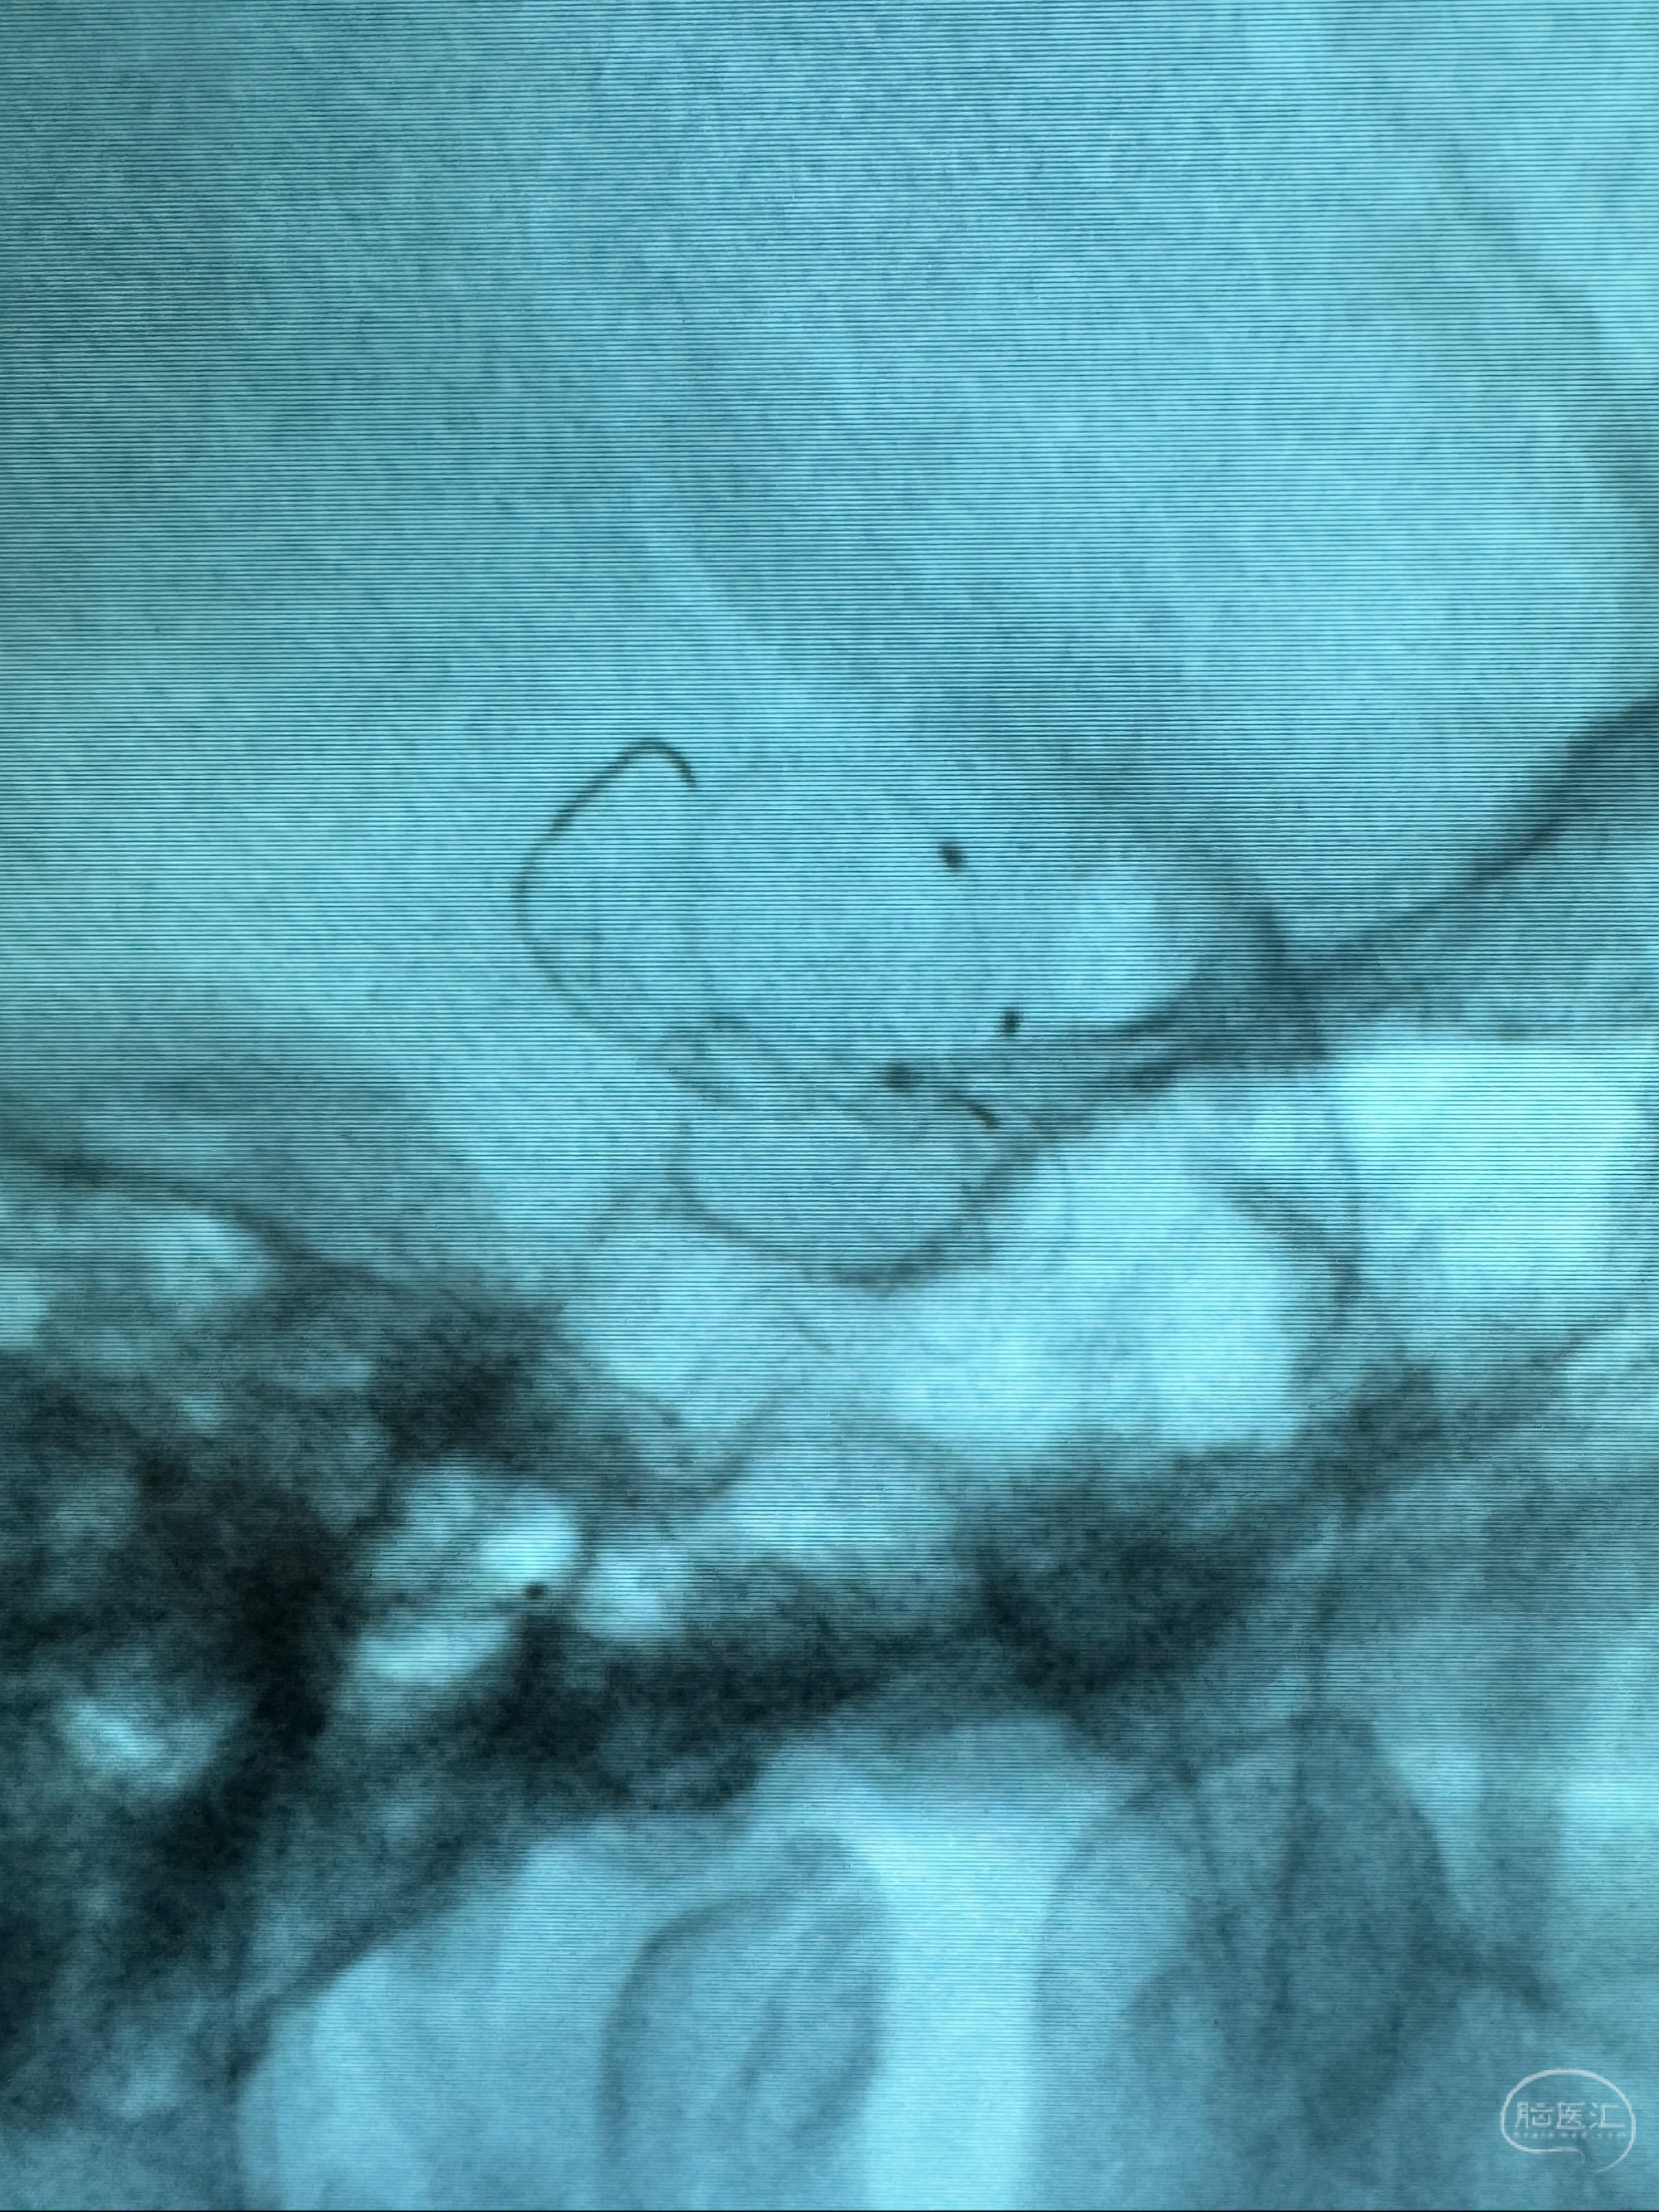

透视可见红圈部分为支架导管的头端

手推冒烟显示支架位置及展开情况,箭头为支架导管的位置

尝试回收支架失败,只能考虑释放支架了

逐帧图像展示歪着脖子释放支架,旁边吩咐助手手机摄影、拍照留像(透视机不能留影像)

接下的视频为释放支架的过程及试图确认支架与血管的关系